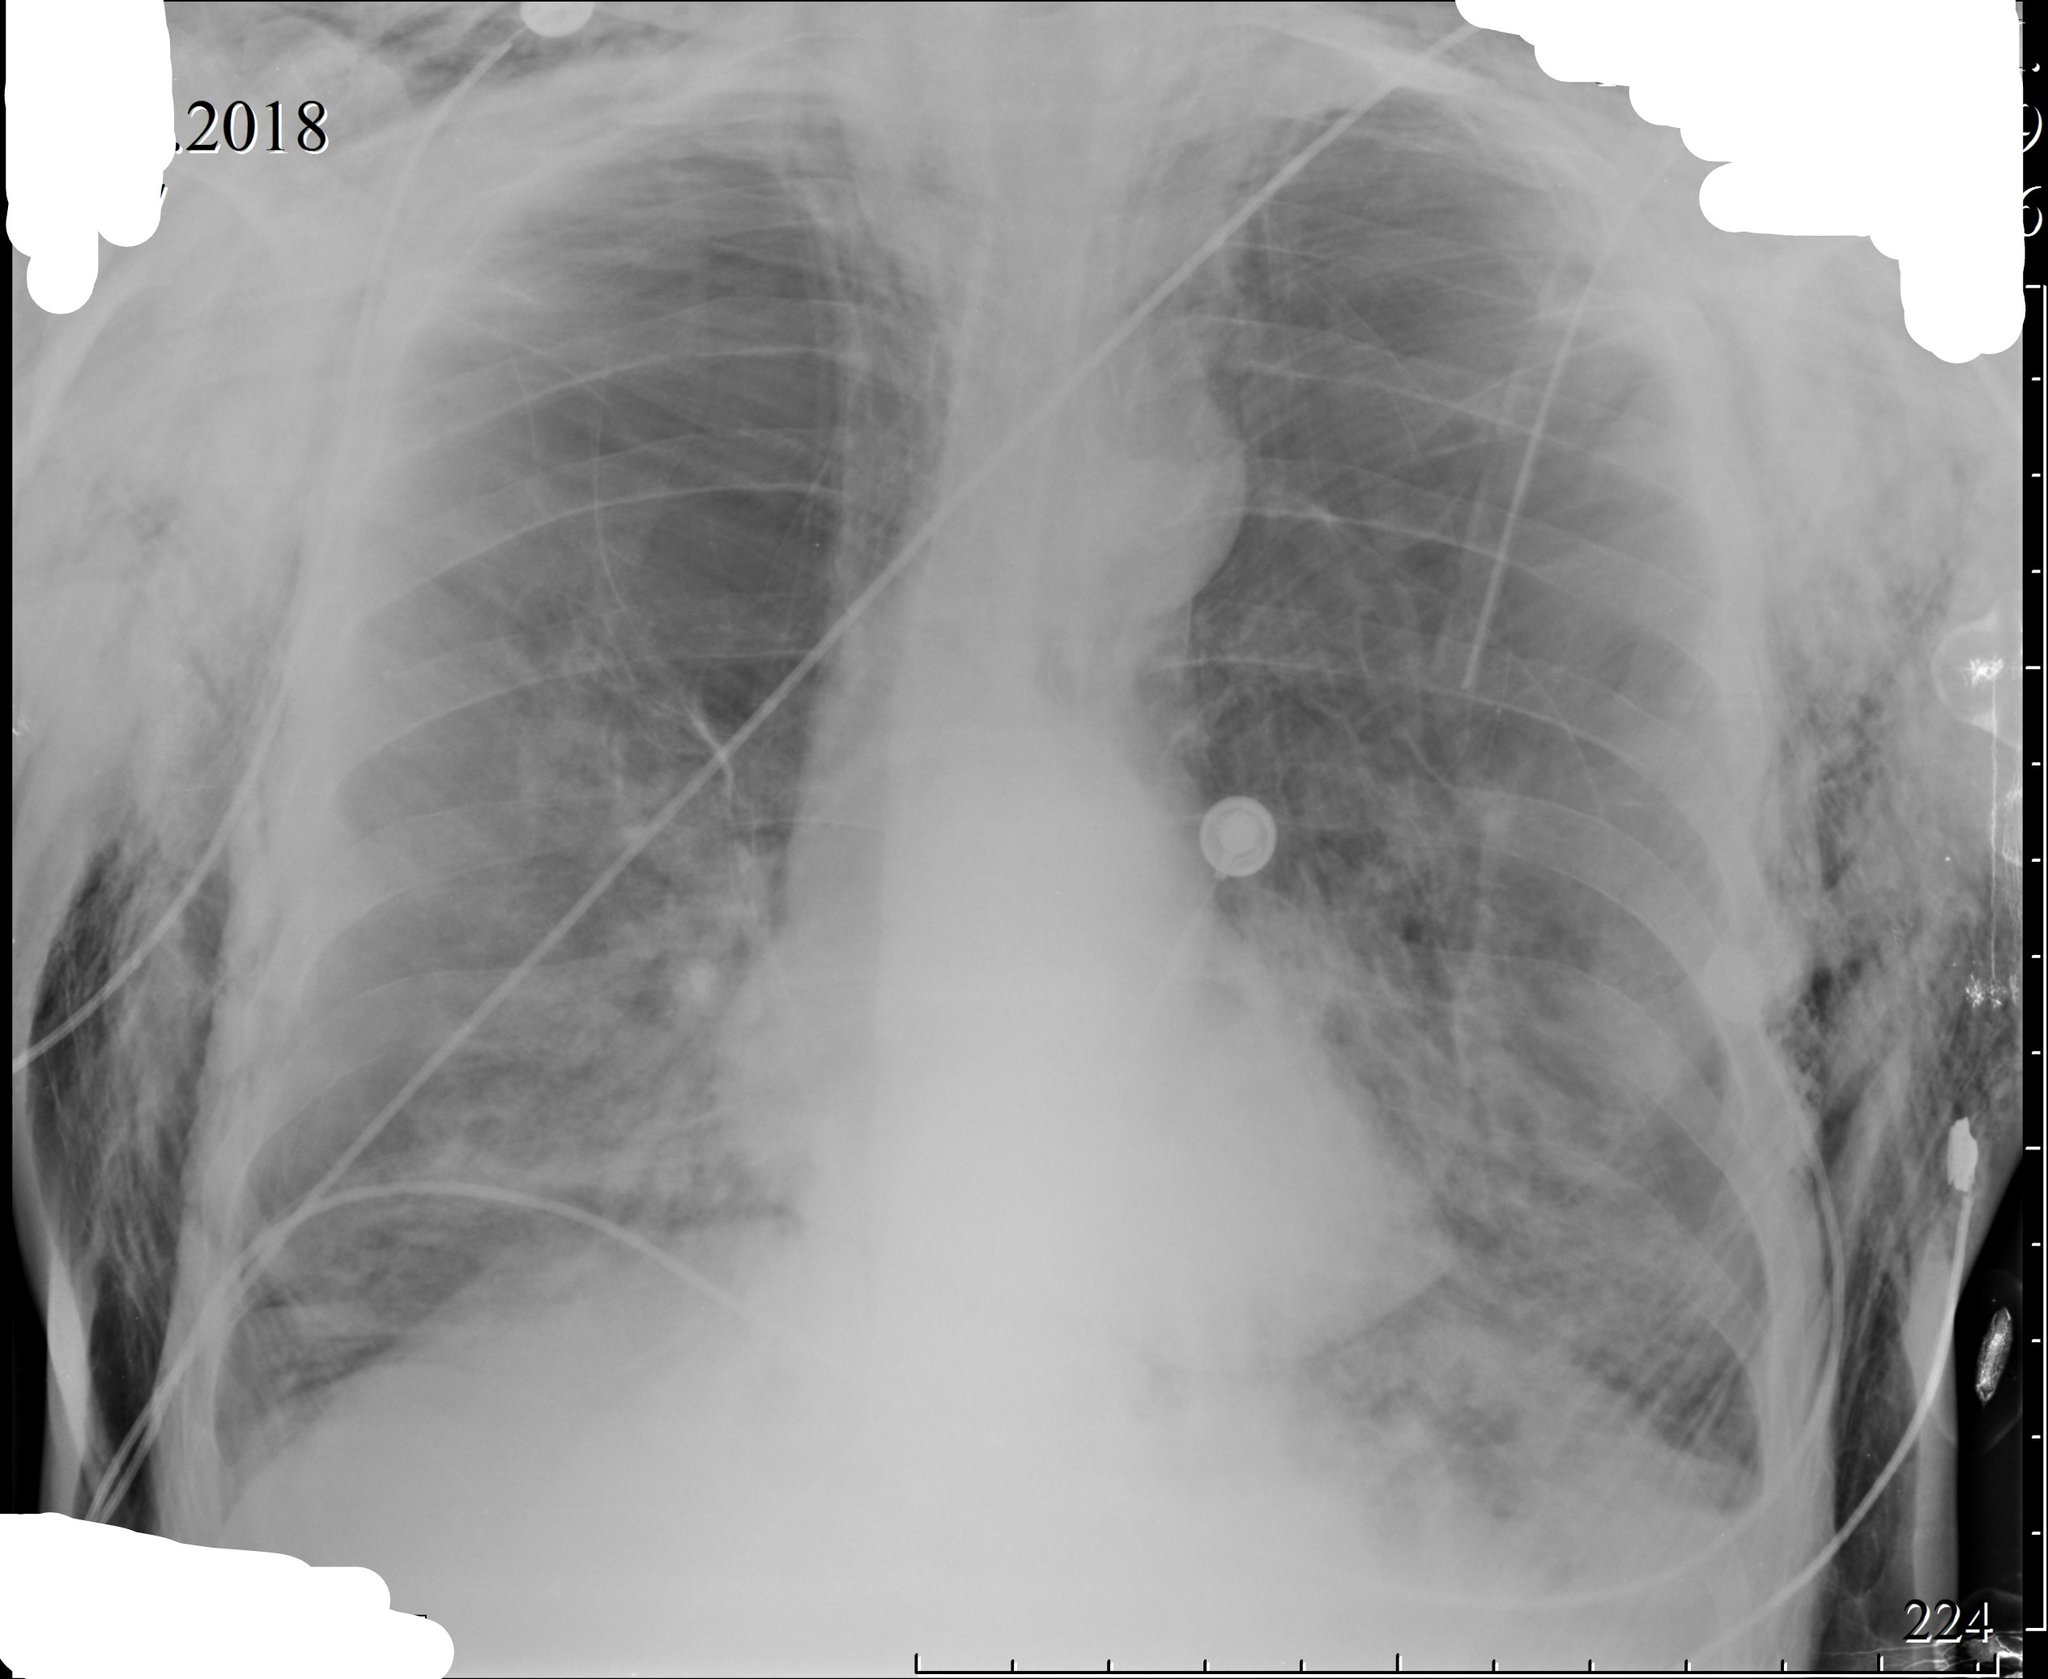

Рентгеновские снимки при врожденной эмфиземе легкого

Раздел: Визуальные уроки